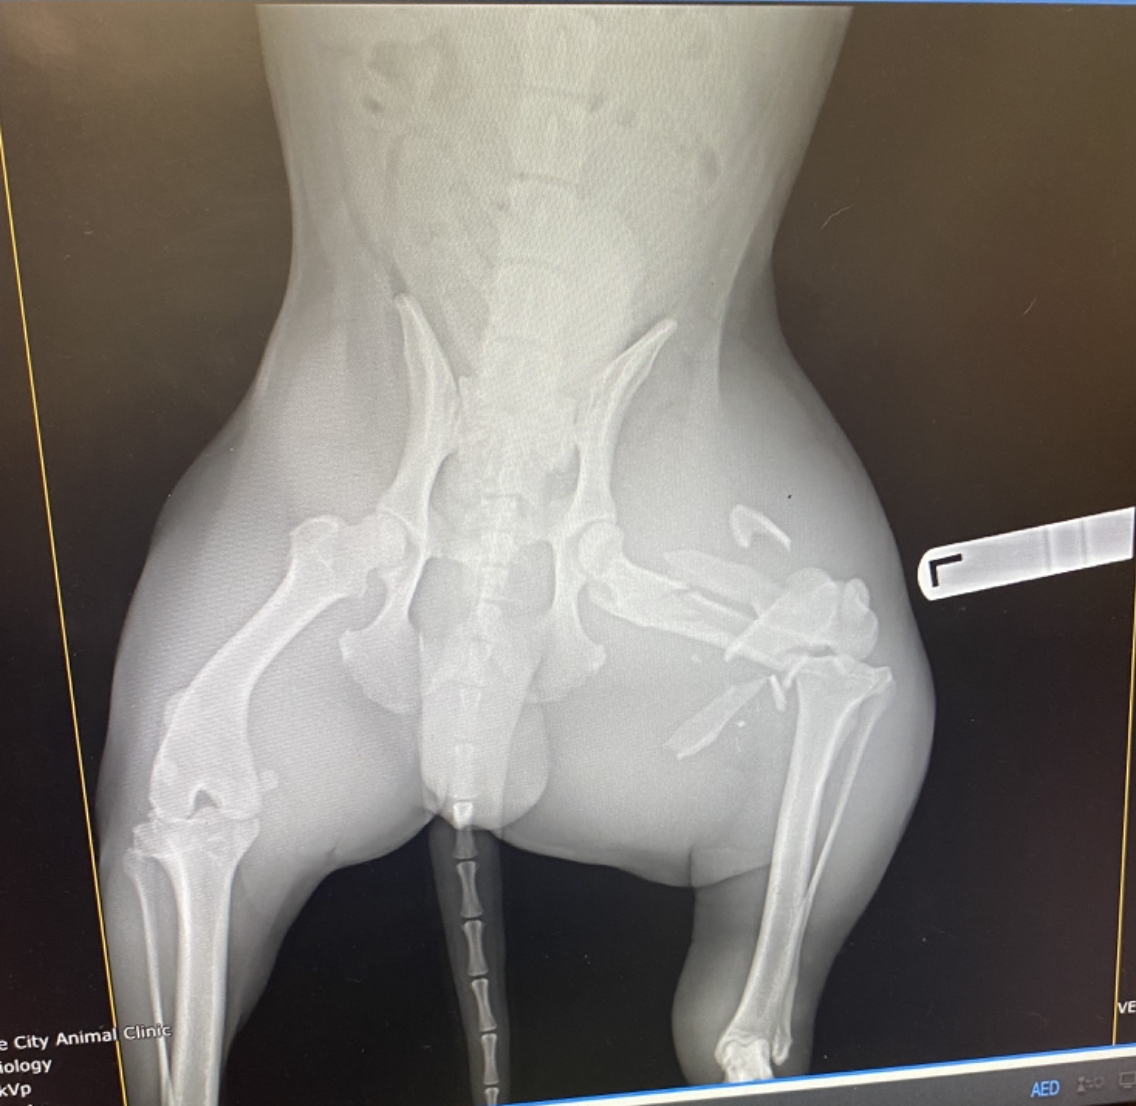

Jase got hit by a vehicle on Saint Joe Rd on Tuesday afternoon. He was lost until Friday when he was found in the back yard. Please help to save his leg from amputation. Dr. Hays from Tampa says he can fix his leg. However, this is going to cost $4200. Thank you so much in advance.